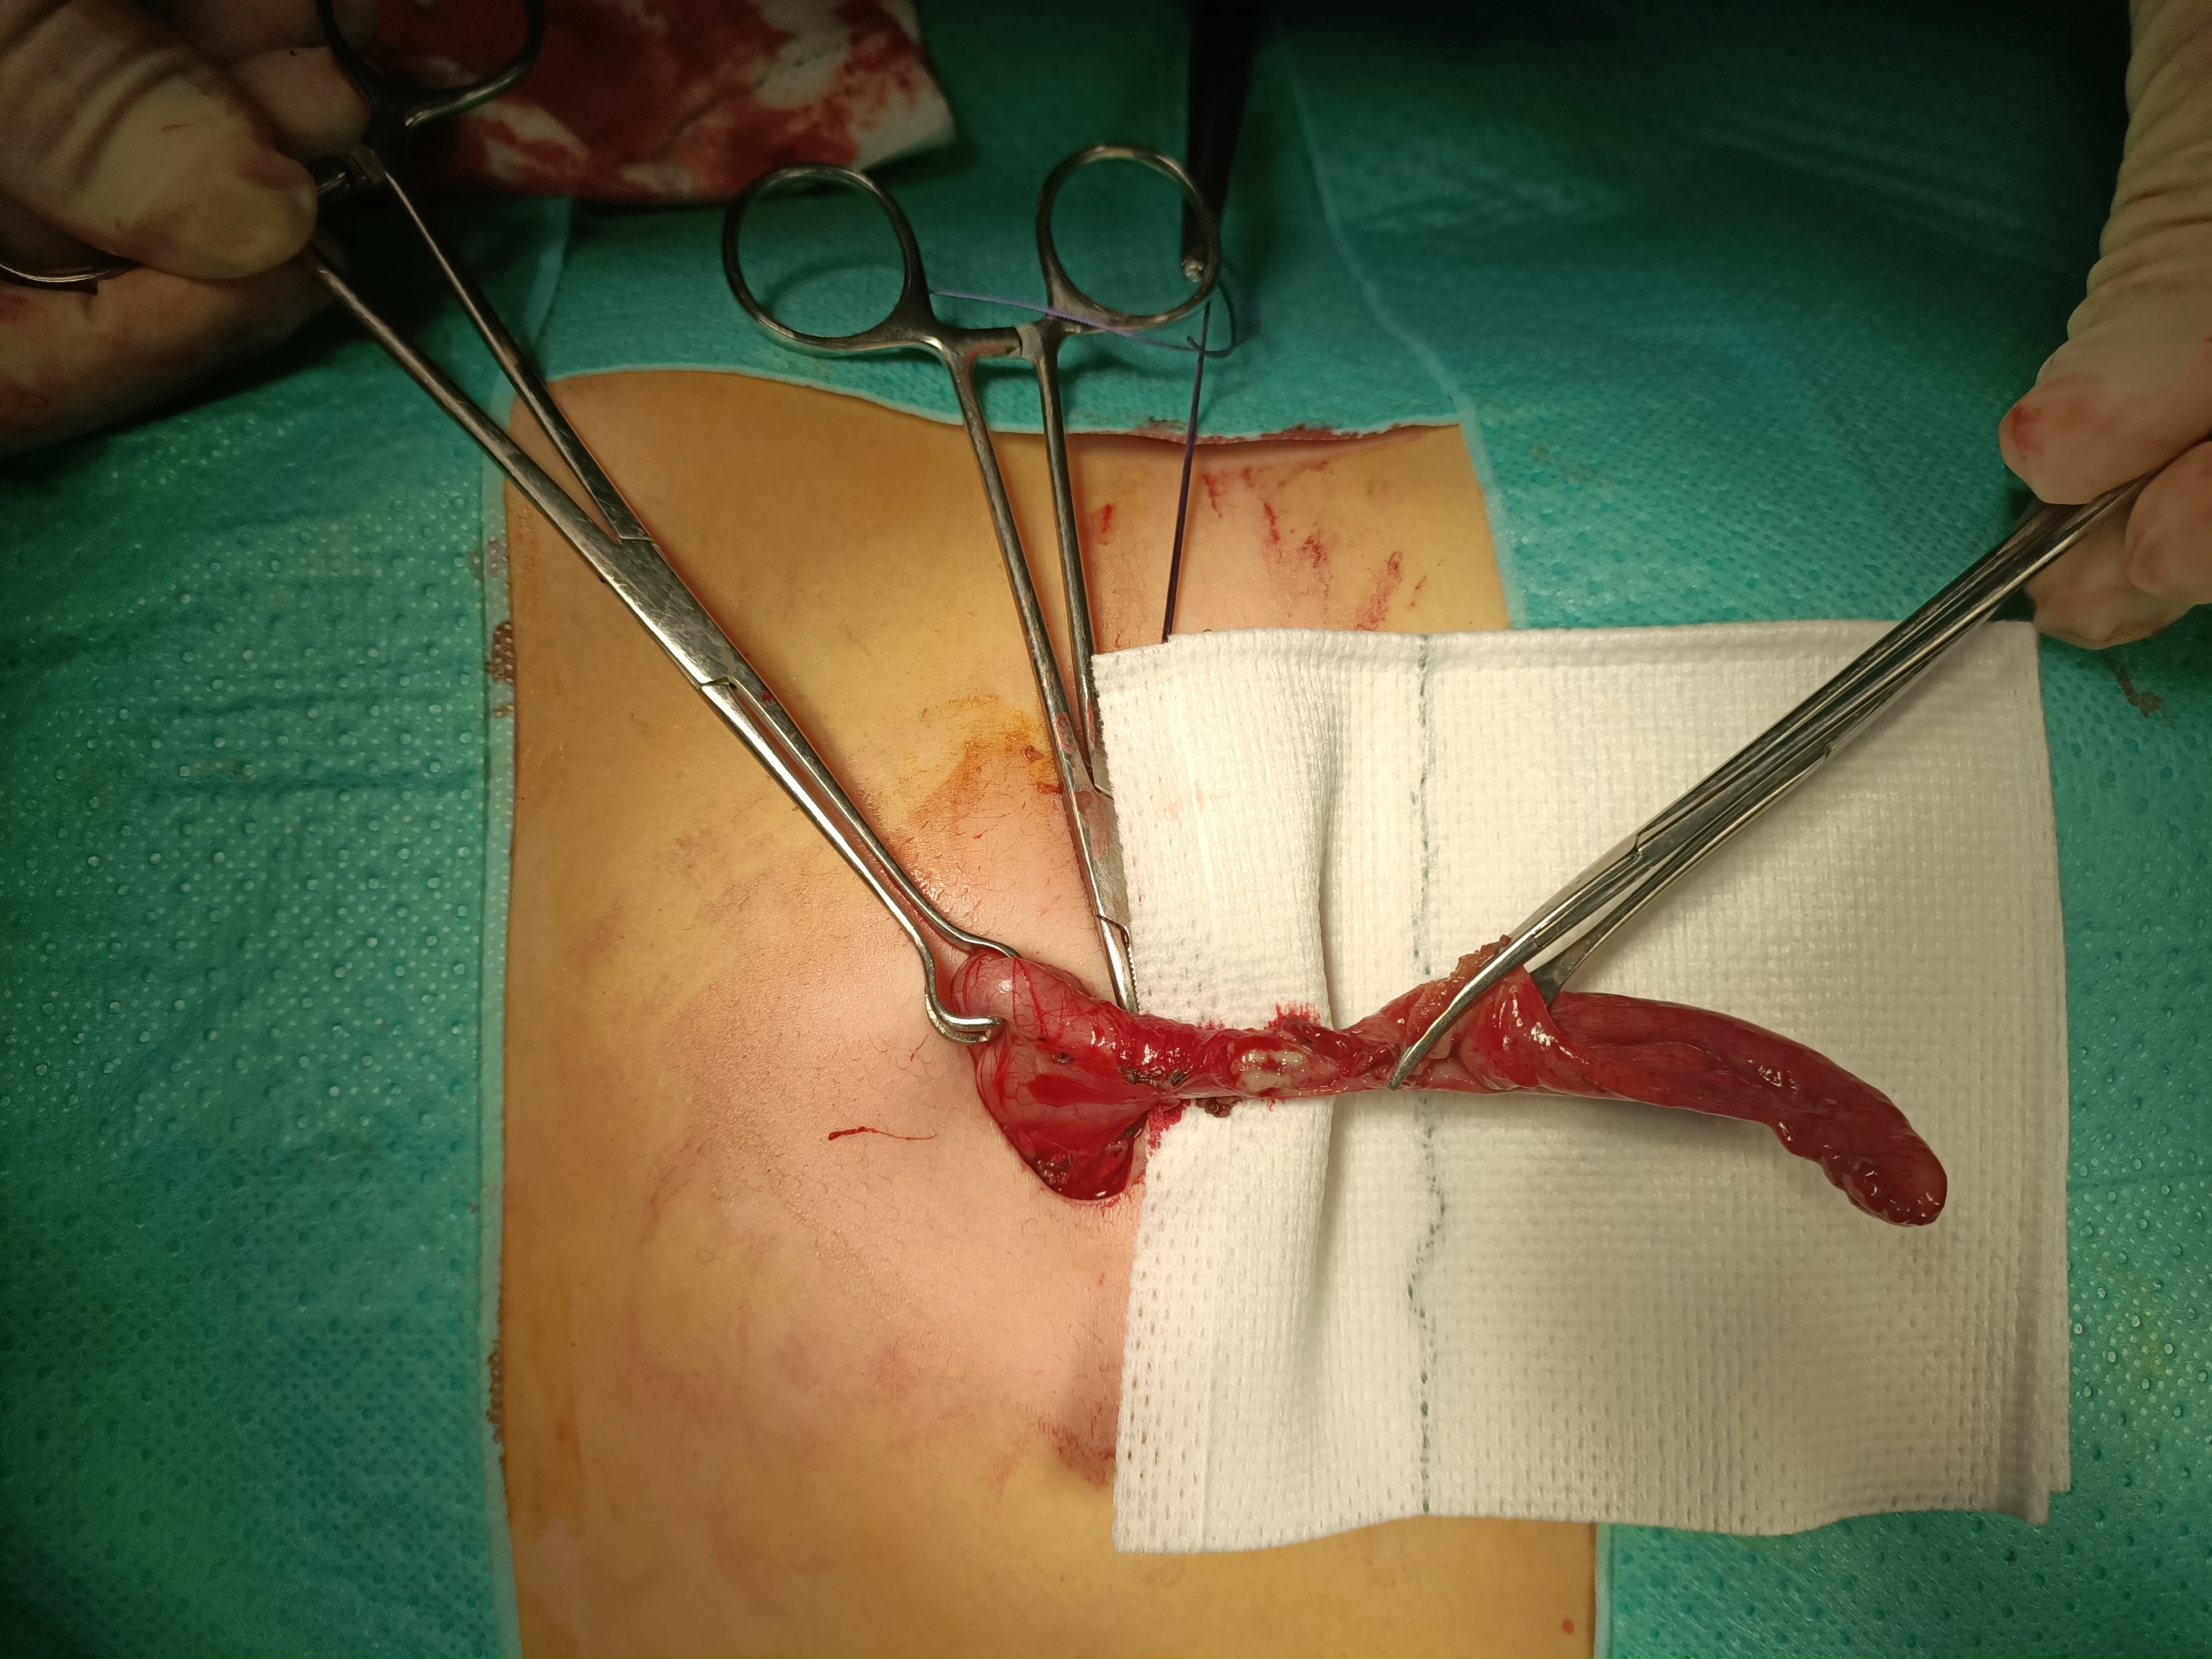

개복술(개복 충수 절제술)은 100년 이상 급성 충수염의 표준 치료법이었다.[90] 이 수술은 하복부 오른쪽 부위에 단일 절개를 가하여 감염된 충수를 제거하는 방식으로 진행된다.[91] 개복술 시 절개 부위는 보통 약 5.08cm 에서 약 7.62cm 정도이다.

개복 충수 절제술 중에는, 충수염이 의심되는 환자는 근육을 완전히 이완시키고 의식을 유지하기 위해 전신 마취를 받는다. 절개 부위는 약 5.08cm 에서 약 7.62cm이며, 엉덩이뼈 위 몇 인치 지점의 오른쪽 하복부에 절개를 가한다. 절개를 통해 복강을 열고 충수를 확인한 후, 외과 의사는 감염된 조직을 제거하고 주변 조직에서 충수를 잘라낸다. 감염 부위를 주의 깊게 면밀히 검사하여 주변 조직에 손상이나 감염의 징후가 없는지 확인한다. 응급 개복 충수 절제술로 관리되는 복잡한 충수염의 경우, 복부 배액(농양 형성을 방지하기 위해 복부에서 외부로 연결하는 임시 튜브)을 삽입할 수 있지만, 이로 인해 입원 기간이 길어질 수 있다.[92] 외과 의사는 절개 부위를 봉합하기 시작한다. 이는 근육을 꿰매고 수술용 스테이플러 또는 봉합사를 사용하여 피부를 봉합하는 것을 의미한다. 감염을 예방하기 위해 절개 부위는 멸균 붕대 또는 수술용 접착제로 덮는다.